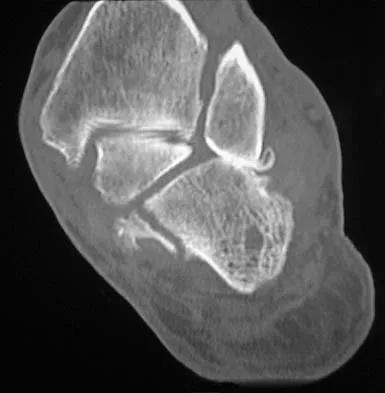

Figures 38a and 38b show the CT scans of a 64-year-old woman. What is the most likely diagnosis?

The CT scans show large cystic lesions in the talus and calcaneus with complete subluxation of the subtalar joint, allowing the calcaneus to slide laterally until it becomes blocked by the fibula. The cause of this subluxation is severe posterior tibial tendon dysfunction. Although no fibular fracture has yet appeared, it can occur with continued stress from the calcaneus. There is, however, a pathologic fracture in the medial calcaneus through a medial degenerative cyst. The joint space is irregular and not symmetrical as would be seen in an inflammatory arthropathy. Cystic lesions are not present in the tibia. No stress fracture is seen in the talus. Coughlin MJ: Sesamoids and accessory bones of the foot, in Coughlin MJ, Mann RA (eds): Surgery of the Foot and Ankle, ed 7. St Louis, MO, Mosby, 1999, pp 437-499.